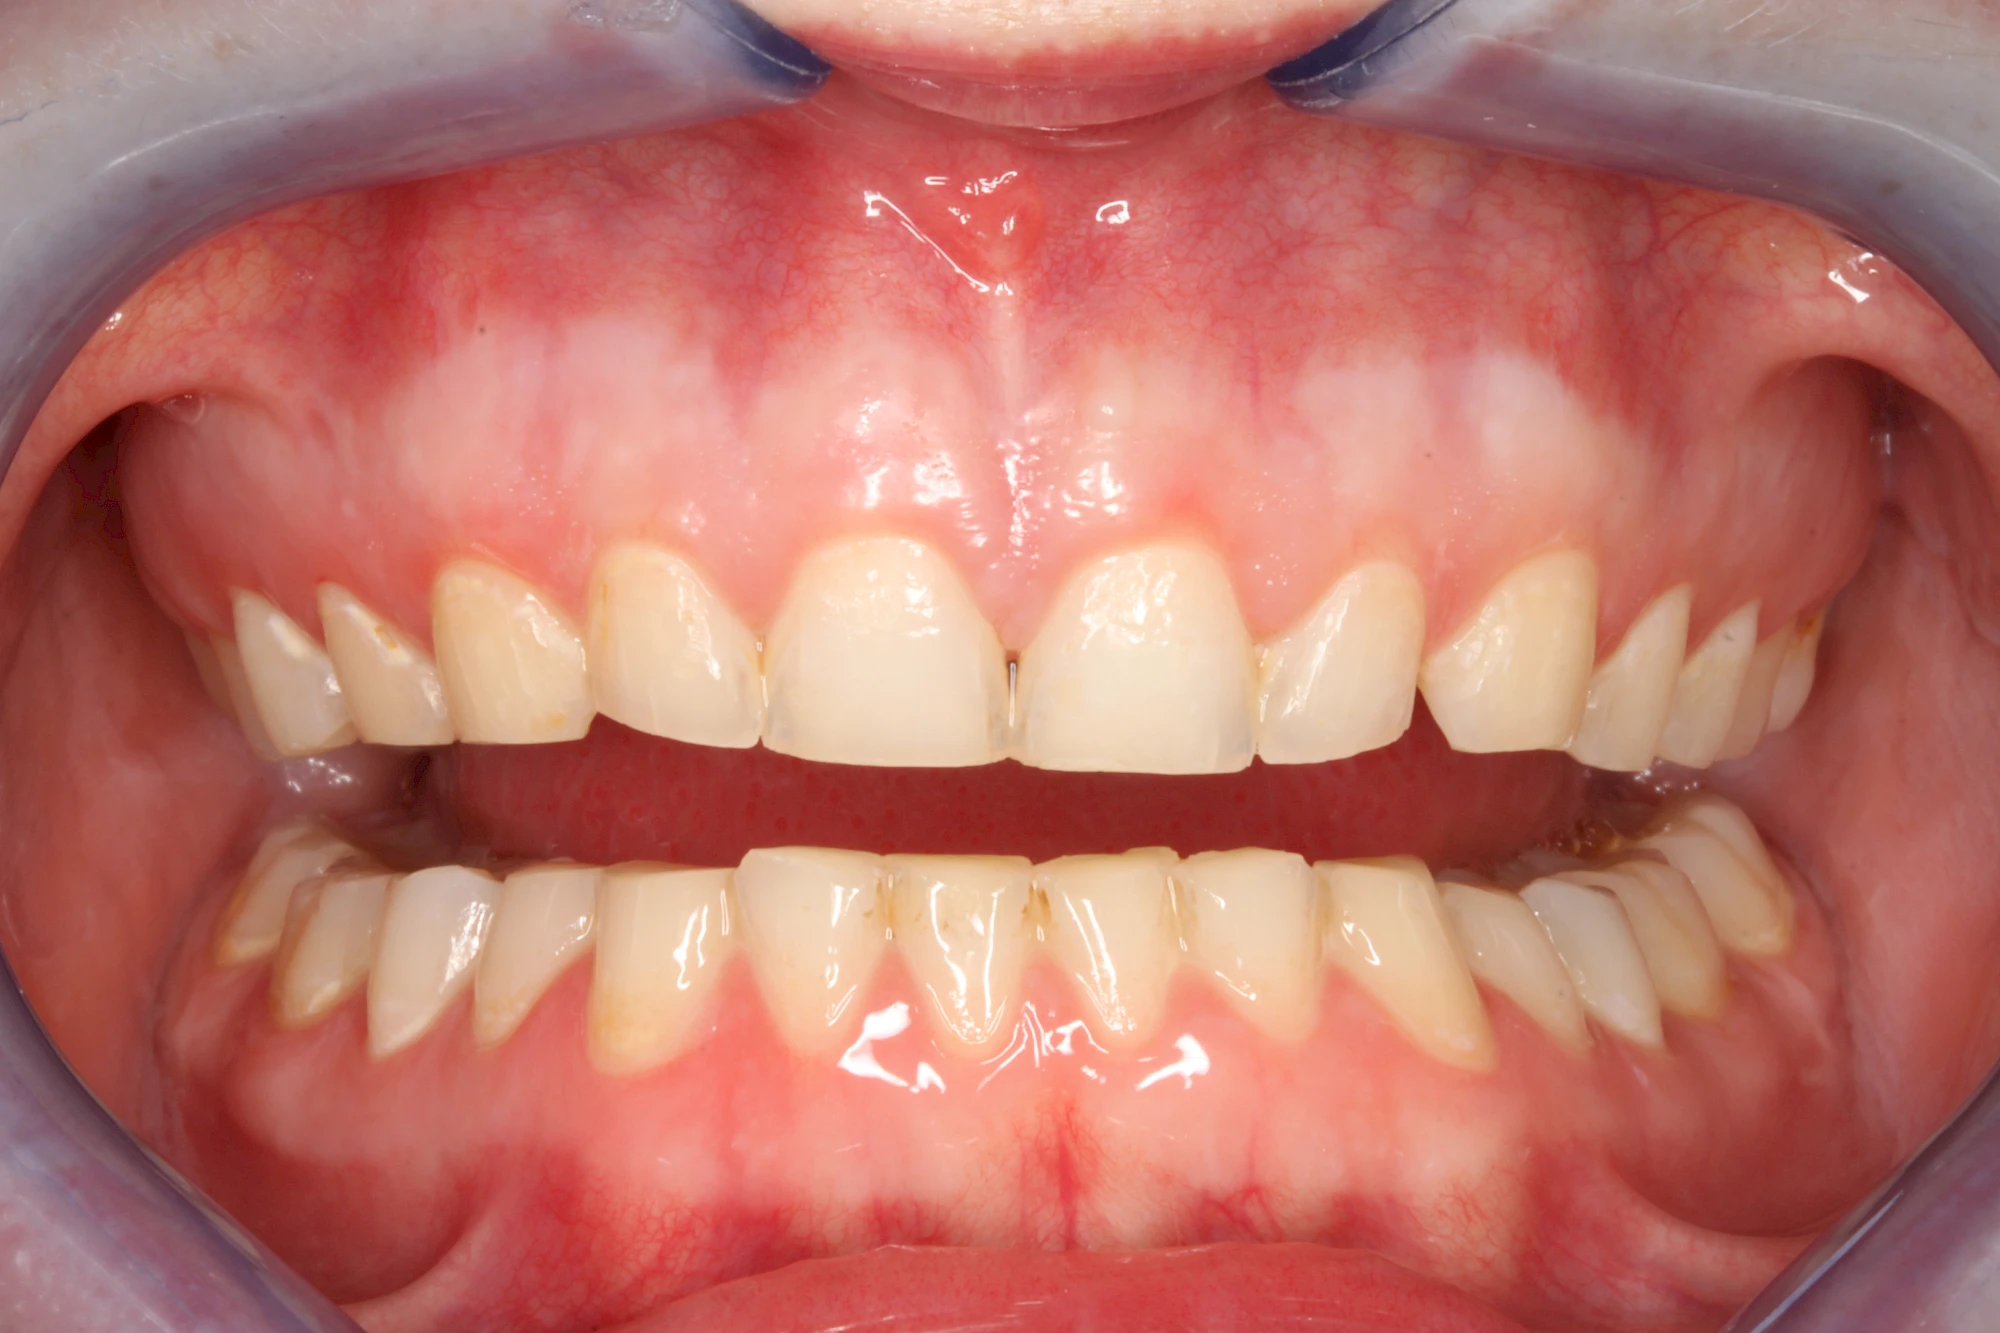

Über die Zeit können verschiedene Prozesse die Zahnhartsubstanzen aufzehren:

- Abnutzung durch Kauen (Abrasion) oder duch durch übermäßiges Knirschen bzw. Pressen (Attrition)

- Säurebedingte Auswaschung (Erosion)

Auswaschung (Erosion) dagegen ist eine Verschleißerscheinung der Zähne aufgrund von immer wiederkehrenden Säureangriffen durch die Nahrung, verstärkt zum Beispiel durch den Genuss säurehaltiger Getränke oder Speisen. Auch bei Menschen mit einer Essstörung (z. B. Bulimie) können die Zähne durch die Magensäure ausgewaschen erscheinen.